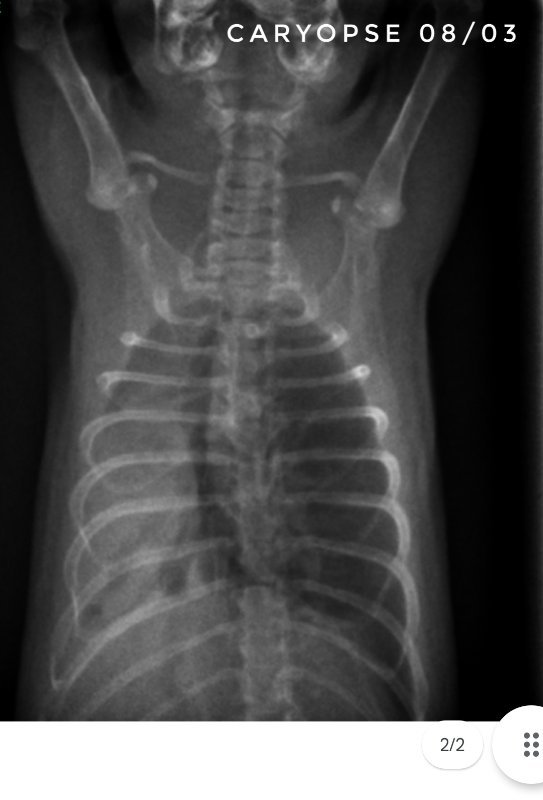

Toujours pour ceux que ça intéresse, les dernières  radios et le suivi du poids (Pyridion a commencé à perdre du poids le 04 mars, traitement changé le 08)

Il nous reste donc 3 malades : Drupe, Caryopse et Pyridion.

Drupe va vraiment mieux, poumons encore touchés mais mieux quand même (mais décidément c'est bien long).

Pyridion a eu un vrai mieux la semaine dernière et grosse dégradation là. Les radios n'ont pas bougé depuis 3 semaines...

Et Caryopse, mon petit nain (180g) va physiquement pas trop mal, c'est à dire qu'il respire vite mais pas pire quoi... par contre ses radios sont... bref, le veto ne s'y attendait pas du tout lui non plus... en gros, petit mieux là où il était touché avant mais dégradation asur le reste du poumon...